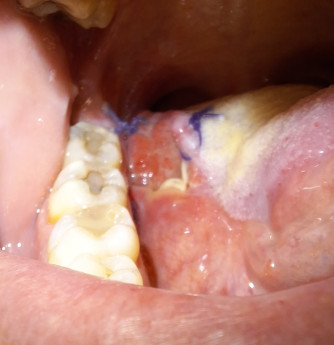

Eenmaal thuis ging het best goed totdat ik dinsdag op woensdag nacht de slaap niet kon vatten vanwege de pijn. Niet te doen en de halve nacht beneden gezeten. Elke beweging met de tong is pijnlijk. Slikken en praten niet te doen. Zelfs de pijnstillers nemen is de hel. De volgende ochtend bel ik direct om 8uur mijn verpleegkundig specialist. Ze vraagt mij om een foto te maken van de tong. Zo gezegd zo gedaan. Ik zet ze een minuut later op de app en met een half uur belt ze al terug. Ons vermoeden werd bevestigd, de hechtingen zijn los gescheurd. Ik heb een open wond, een soort krater, in mijn mond en dat doet pijn... heel veel pijn. De inwendige hechtdraden zijn zichtbaar en de bovenkant van de tong zit niet meer aan de onderkant. Zij geeft aan dat de pijn 2 weken kan aanhouden en dat ik een spiegel moet opbouwen met pijnstillers. Voor nood mag ik Oxycodon 5mg gebruiken tot 6x per dag. De eerste dagen heb ik dit ook echt nodig. Veel slapen en duf. Eten gaat moeizaam maar ik moet wel blijven eten want we zitten inmiddels sinds de diagnose op min 12kilo. Bezoek is ook geen optie want ik probeer zo min mogelijk te praten. Na een helse week merk ik dat het de goede kant op gaat. De tong lijkt zich goed te herstellen. Bizar hoe snel dit gaat. Ik kan afbouwen met de pijnstillers en het eten van iets vaster voedsel. Nu wachten op de uitslag.